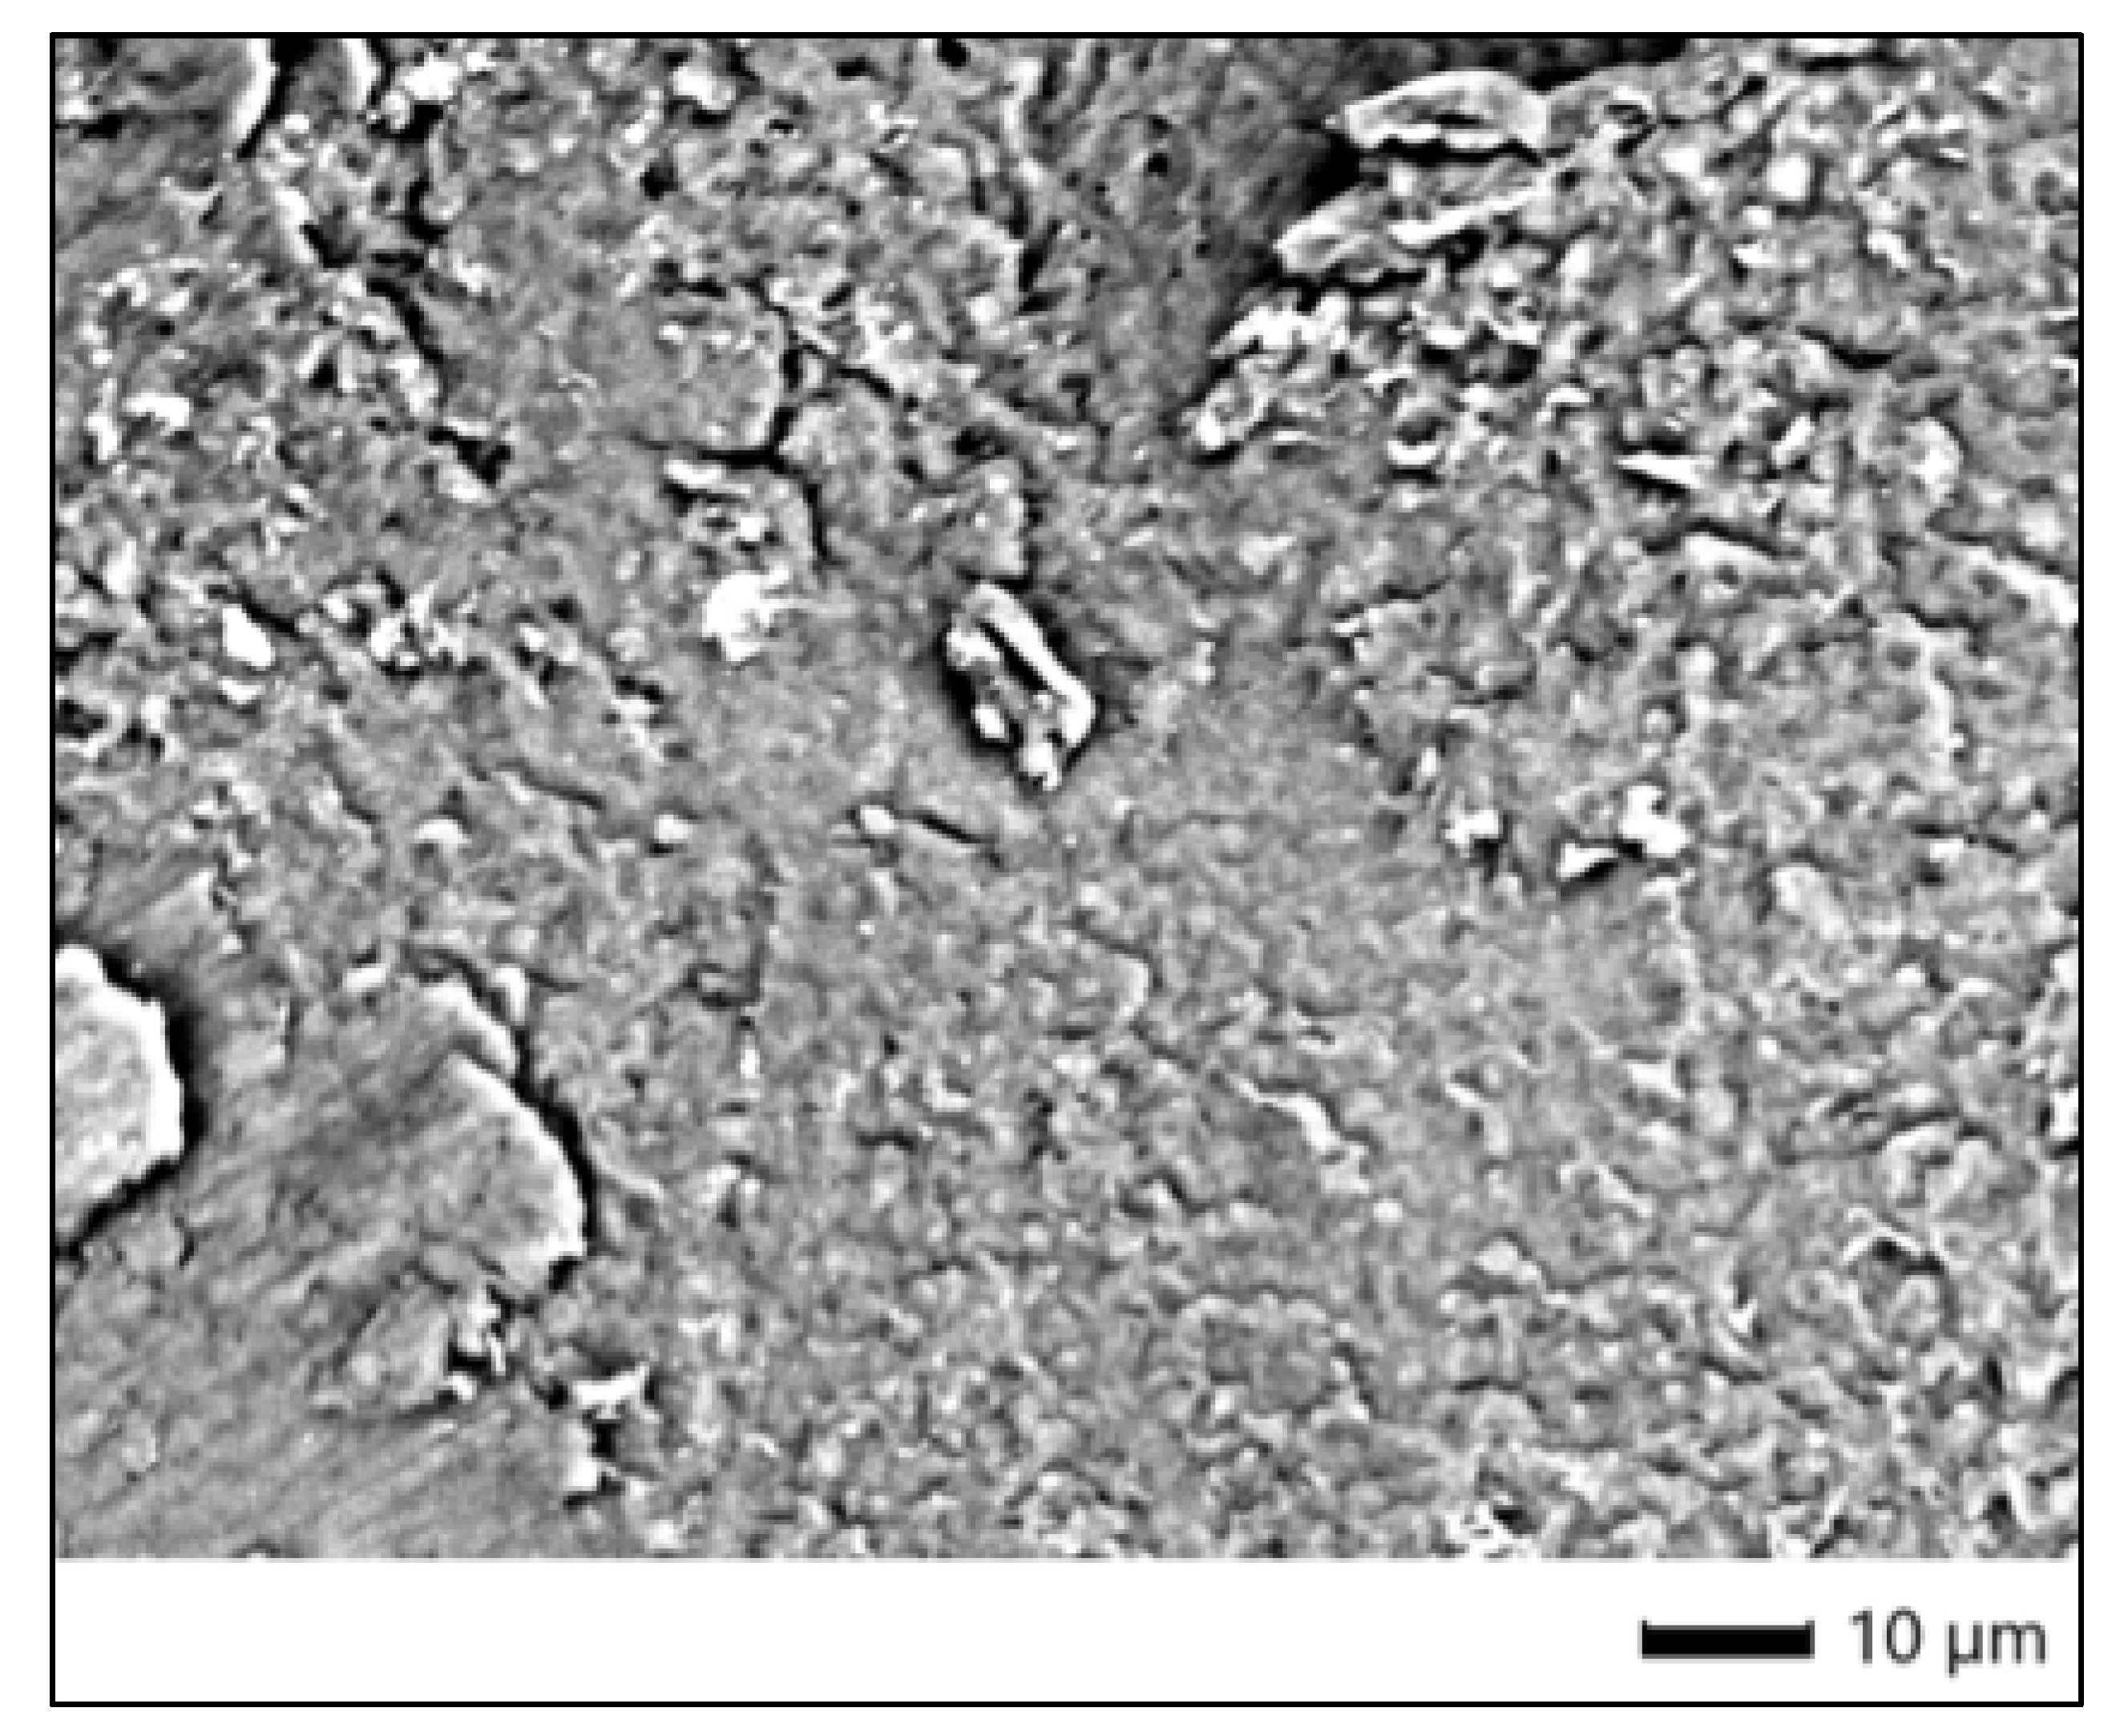

3.9. BlancOne Ultra+ Group (SEM Morphological Evaluation)

SEM examination of the control specimen for the BlancOne Ultra+ group (9C) revealed a compact enamel surface with distinct morphological characteristics. At ×1100 magnification, the enamel exhibited a moderately rough texture, characterized by a dense network of superficial cracks and granular surface disruptions. These features suggest some degree of structural irregularity, possibly related to sample dehydration or pre-existing surface stress, but no aggressive material loss or prism disintegration was evident. Overall, the enamel surface preserved its structural continuity, indicating it had not been subjected to bleaching-induced degradation (Figure 5).

Fitting ratios: All values were below 0.05, confirming the reliability of the elemental quantification. The relatively high and uniform levels of Ca and P across all spots confirm a stable and intact mineral phase. Despite the presence of superficial cracks visible in SEM, the elemental distribution did not suggest significant mineral loss or chemical alteration. These findings validate the sample’s suitability as a control for comparison with bleached specimens.